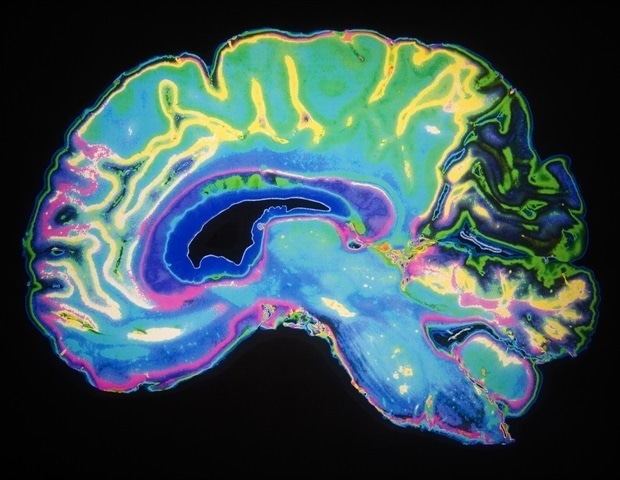

По данным Ассоциации Альцгеймера, более семи миллионов американцев страдают болезнью Альцгеймера, причем две трети из них — женщины. Лаборатория О'Бэниона в Институте неврологии Дель Монте Рочестерского университета уже давно изучает это заболевание и более внимательно изучает различия между мужским и женским мозгом.

Новое исследование, проведенное О'Бэнионом и аспиранткой неврологии Лией Кальсинес-Родригес обнаружила, что иммунные клетки головного мозга, известные как микроглия, действуют по-разному в мужском и женском мозге с болезнью Альцгеймера и, по-видимому, вызывают остаточный вред в женском мозге. Как описано в их недавней статье в Journal of Neuroinflammation, они обнаружили, что у мышей, когда микроглия реагирует на амилоидные бляшки - липкие скопления белка, которые накапливаются в мозгу при болезни Альцгеймера. заболевание - женская микроглия экспрессирует больше генов, связанных с интерфероном.

В организме интерфероны известны своей ролью в борьбе с вирусными инфекциями, однако роль интерферонов при болезни Альцгеймера неизвестна. Предыдущие исследования показали, что передача сигналов интерферона может вызывать нейровоспаление и повреждать синапсы, связи между нейронами. Исследователи полагают, что, когда микроглия поглощает амилоидные бляшки, они могут подвергаться воздействию ДНК или. РНК, ошибочно принимают ее за вирус, и это может привести к тому, что клетки высвободят интерферон, хотя точная причина и функция интерферона при болезни Альцгеймера остаются неясными.

Это исследование также показало, что женская микроглия оставляет после себя более крупные и нерегулярные бляшки, которые повреждают больше нейронных связей, чем в мужском мозге.